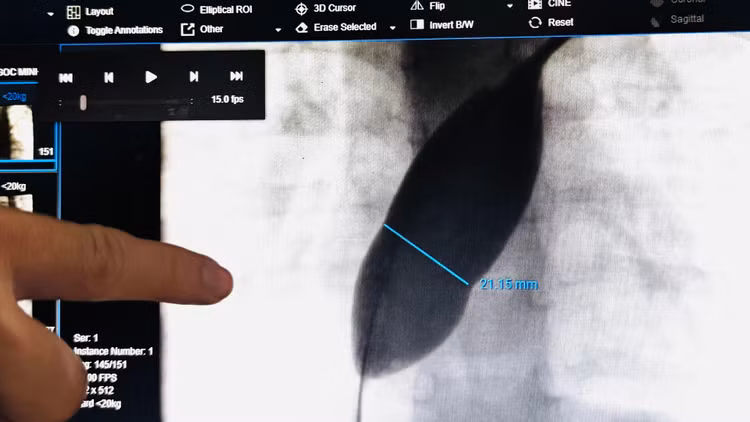

Đây là một trường hợp thông liên nhĩ phức tạp với kích thước lỗ thông rất lớn (#21mm) và rìa mỏng, gây khó khăn cho can thiệp thông tim. Bệnh nhi đã được hội chẩn và chuẩn bị các phương án điều trị tốt nhất cho bé.

Hình ảnh thông liên nhĩ lỗ lớn trên phim chụp - Ảnh BVCC